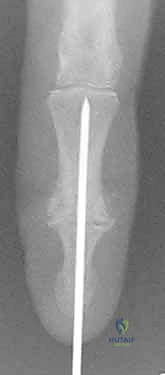

- Kirschner Wire (K-wire) Fixation:

- Advantages: Simplicity of technique, ready availability, low-cost implants. Historically, fusion rates up to 99% have been reported.

- Disadvantages: Less rigid fixation, often requiring additional external immobilization (splint/cast) which can lead to stiffness in surrounding joints. Higher risk of infection (superficial pin site, deep wound, osteomyelitis). Potential for pin migration. Minimal compression across the fusion site, which is biomechanically less favorable.